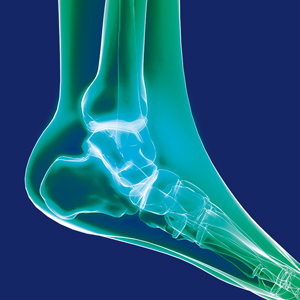

Sprunggelenke

Viele Beschwerden am oberen Sprunggelenk können durch eine Sprunggelenkarthroskopie behoben werden (Abb. 8). Hierzu gehören beispielsweise Gelenkblockaden durch freie Gelenkkörper, Knorpelschäden (s. hierzu Kapitel Knorpeltherapie unter Kniegelenk), Einklemmungsschmerzen durch Wucherungen der Gelenkschleimhaut oder Knochensporne, Osteochondrosis dissecans. In seltenen Fällen ist es erforderlich, das Sprunggelenk durch einen vorderen Schnitt oder sogar eine Osteotomie des Innenknöchels zu eröffnen.